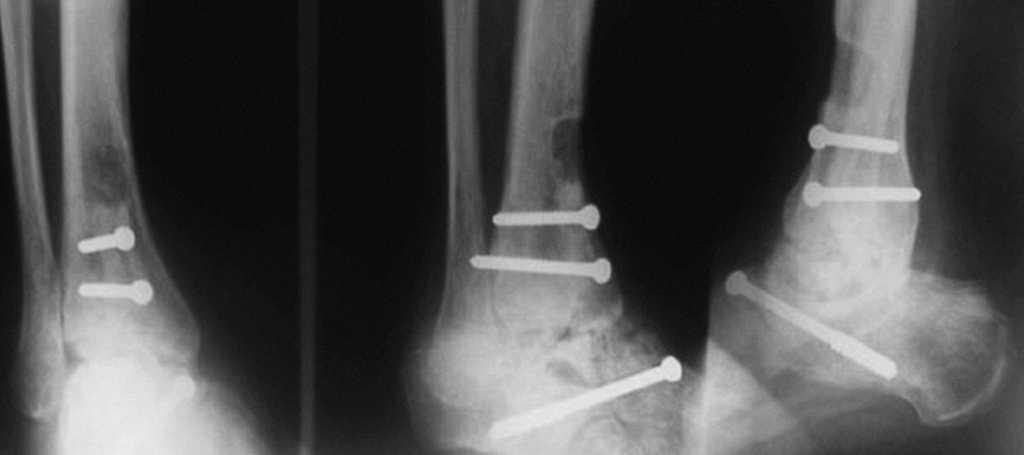

En las fracturas del cuerpo del astrágalo (7 casos) se realizó reducción abierta mediante un abordaje medial con osteotomía del maléolo tibial para visualizar todos los planos de la fractura y fijación interna (RAFI) con tornillos o agujas de Kirschner, o ambos. En 2 casos se realizó un abordaje bilateral debido a la complejidad de la fractura (fig. 6).

Fig. 6. --Fractura abierta de cuello de astrágalo (tipo III de Hawkins) y tratamiento realizado. Radiografías a los 16 meses.

Fig. 6. --Open fracture of the astragalus neck (Hawkins type III) and treatment carried out. Radiographies at 16 months.

En las fracturas del cuello del astrágalo (10 casos) se realizó RAFI con tornillos y agujas de Kirschner. En 4 casos el abordaje fue por vía medial; en 2 fue bilateral (medial y lateral); en 3 se usaron tornillos percutáneos canulados a compresión insertados desde posterior a anterior, y 1 caso en el que se optó por la tracción transcalcánea.